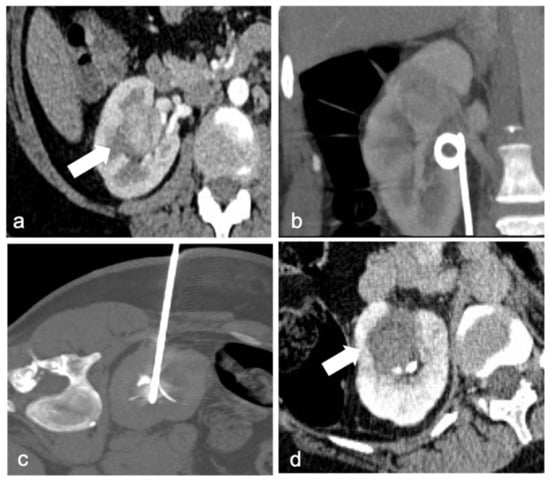

Damage to nearby organs can occur as well: for example, if the renal mass is too close to the bowel, hydro-dissection (Figure 3) (for instance, injecting a glucose solution) could be a strategy to widen the space between the lesion and the organ and minimize possible lesions.

Figure 3.

Arterial phase MRI shows a contrast enhancing anterior right kidney mass (arrow) in a 63-year-old man (a). Due to renal mass proximity to hepatic colon flexure, hydrodissection is obtained with 500 mL of glucose solution (double arrow, (b)). RFA is then performed with margin of safety between the probe and the colon (c). A follow-up MRI 2 months later revealed the necrotic mass (arrows) with no evidence of residual or recurrent tumor in the ablation zone: digital subtraction contrast-enhanced MRI (d) and T2w sequence (e).